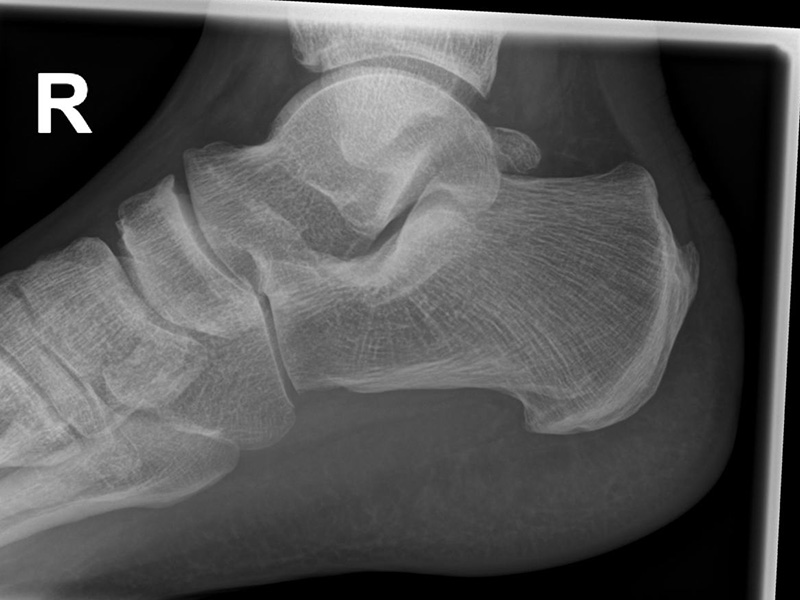

Böhler-Winkel (Syn. Tubergelenkwinkel)

Es wird eine Linie vom Proc. ant. calcanei zur dorsalen Facette des Subtalargelenks gezogen (rot). Die zweite Linie verläuft von der kranialen Begrenzung des Tuber calcanei zum Subtalargelenk (gelb). Gemessen wird der nach dorsal offene Winkel zwischen den beiden Linien (Norm: 22-48° 9).